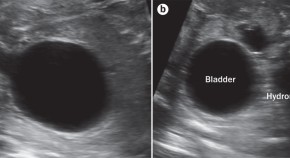

• Lower urinary tract obstruction is a morbid congenital anomaly that can be treated prenatally. Kilby & Morris discuss the importance of accurate diagnosis and case selection to optimize outcomes ofin utero intervention, before reviewing the evidence and outcome data for in uterovesicostomy, vesicoamniotic shunting and fetal cystoscopy.